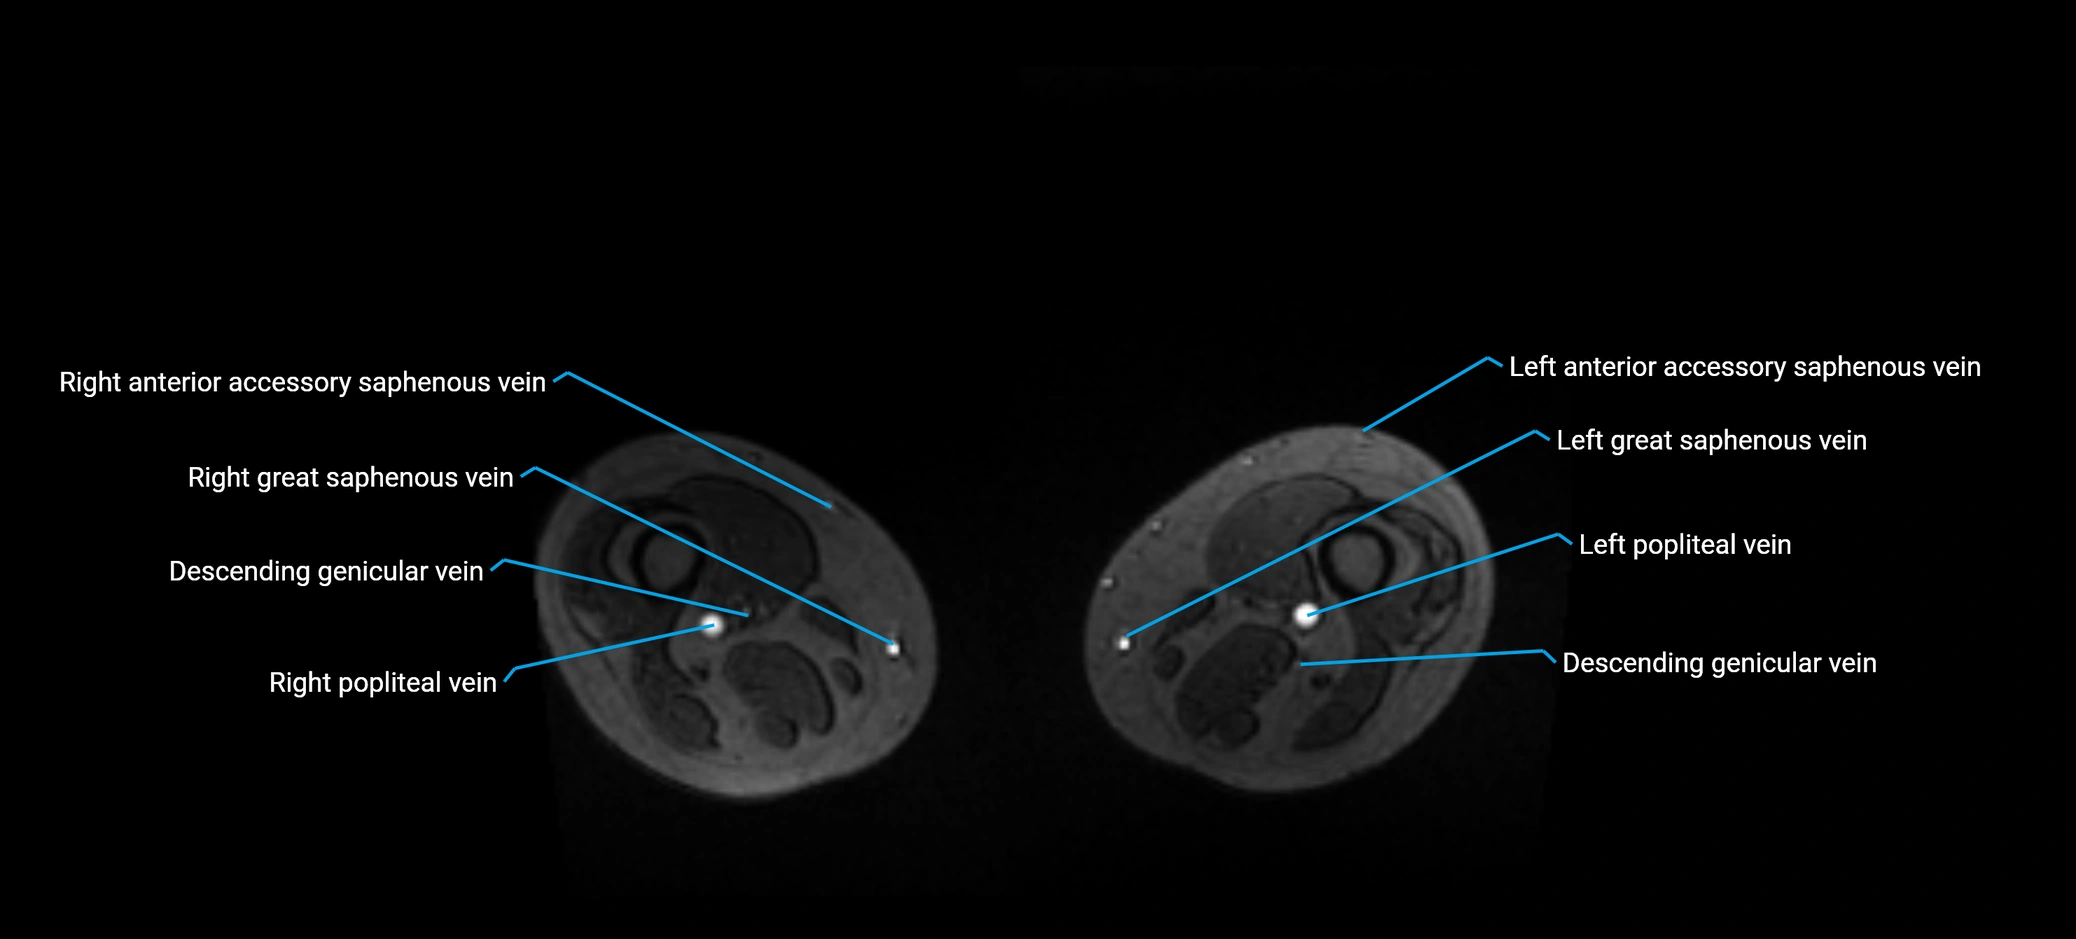

MRI image

image